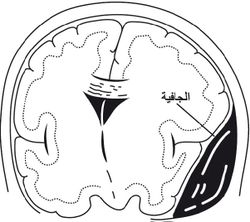

النزف السحائي Intracranial hemorrhage هو النزف الذي يحدث بين الطبقات السحائية، وهي ثلاث طبقات تحيط بالدماغ والنخاع الشوكي، وتقع بينهما وبين البنى العظمية المحيطة بهما (الجمجمة والقناة الفقرية). والطبقات السحائية من الخارج إلى الداخل هي: الجافية dura، والعنكبوتية arachnoid، والحنونية pia.[1]

النزف تحت الجافية وفيه يتجمع الدم بين الجافية والدماغ. وهو أكثر شيوعاً من النزف فوق الجافية بنحو 10 مرات. ويحدث عادة عندما يؤدي رضّ دماغي إلى تمزق أحد (أو بعض) الأوردة التي تعبر الفراغ تحت الجافية. ومن العوامل المؤهبة لحدوث هذا النوع من النزف وجود ضمور دماغي أو انخفاض الضغط داخل القحف (إذ تؤدي هاتان الحالتان إلى تمطط الأوردة في الفراغ تحت الجافية مما يجعلها أكثر عرضة للتمزق)، ومن العوامل الأخرى اضطرابات التخثر والكحولية.

يعتمد رئيساً على تصوير الدماغ (التصوير الطبقي المحوري والرنين المغنطيسي MRI)، وفيه يظهر النزف عادة على شكل تجمع هلالي بين الجمجمة والدماغ.